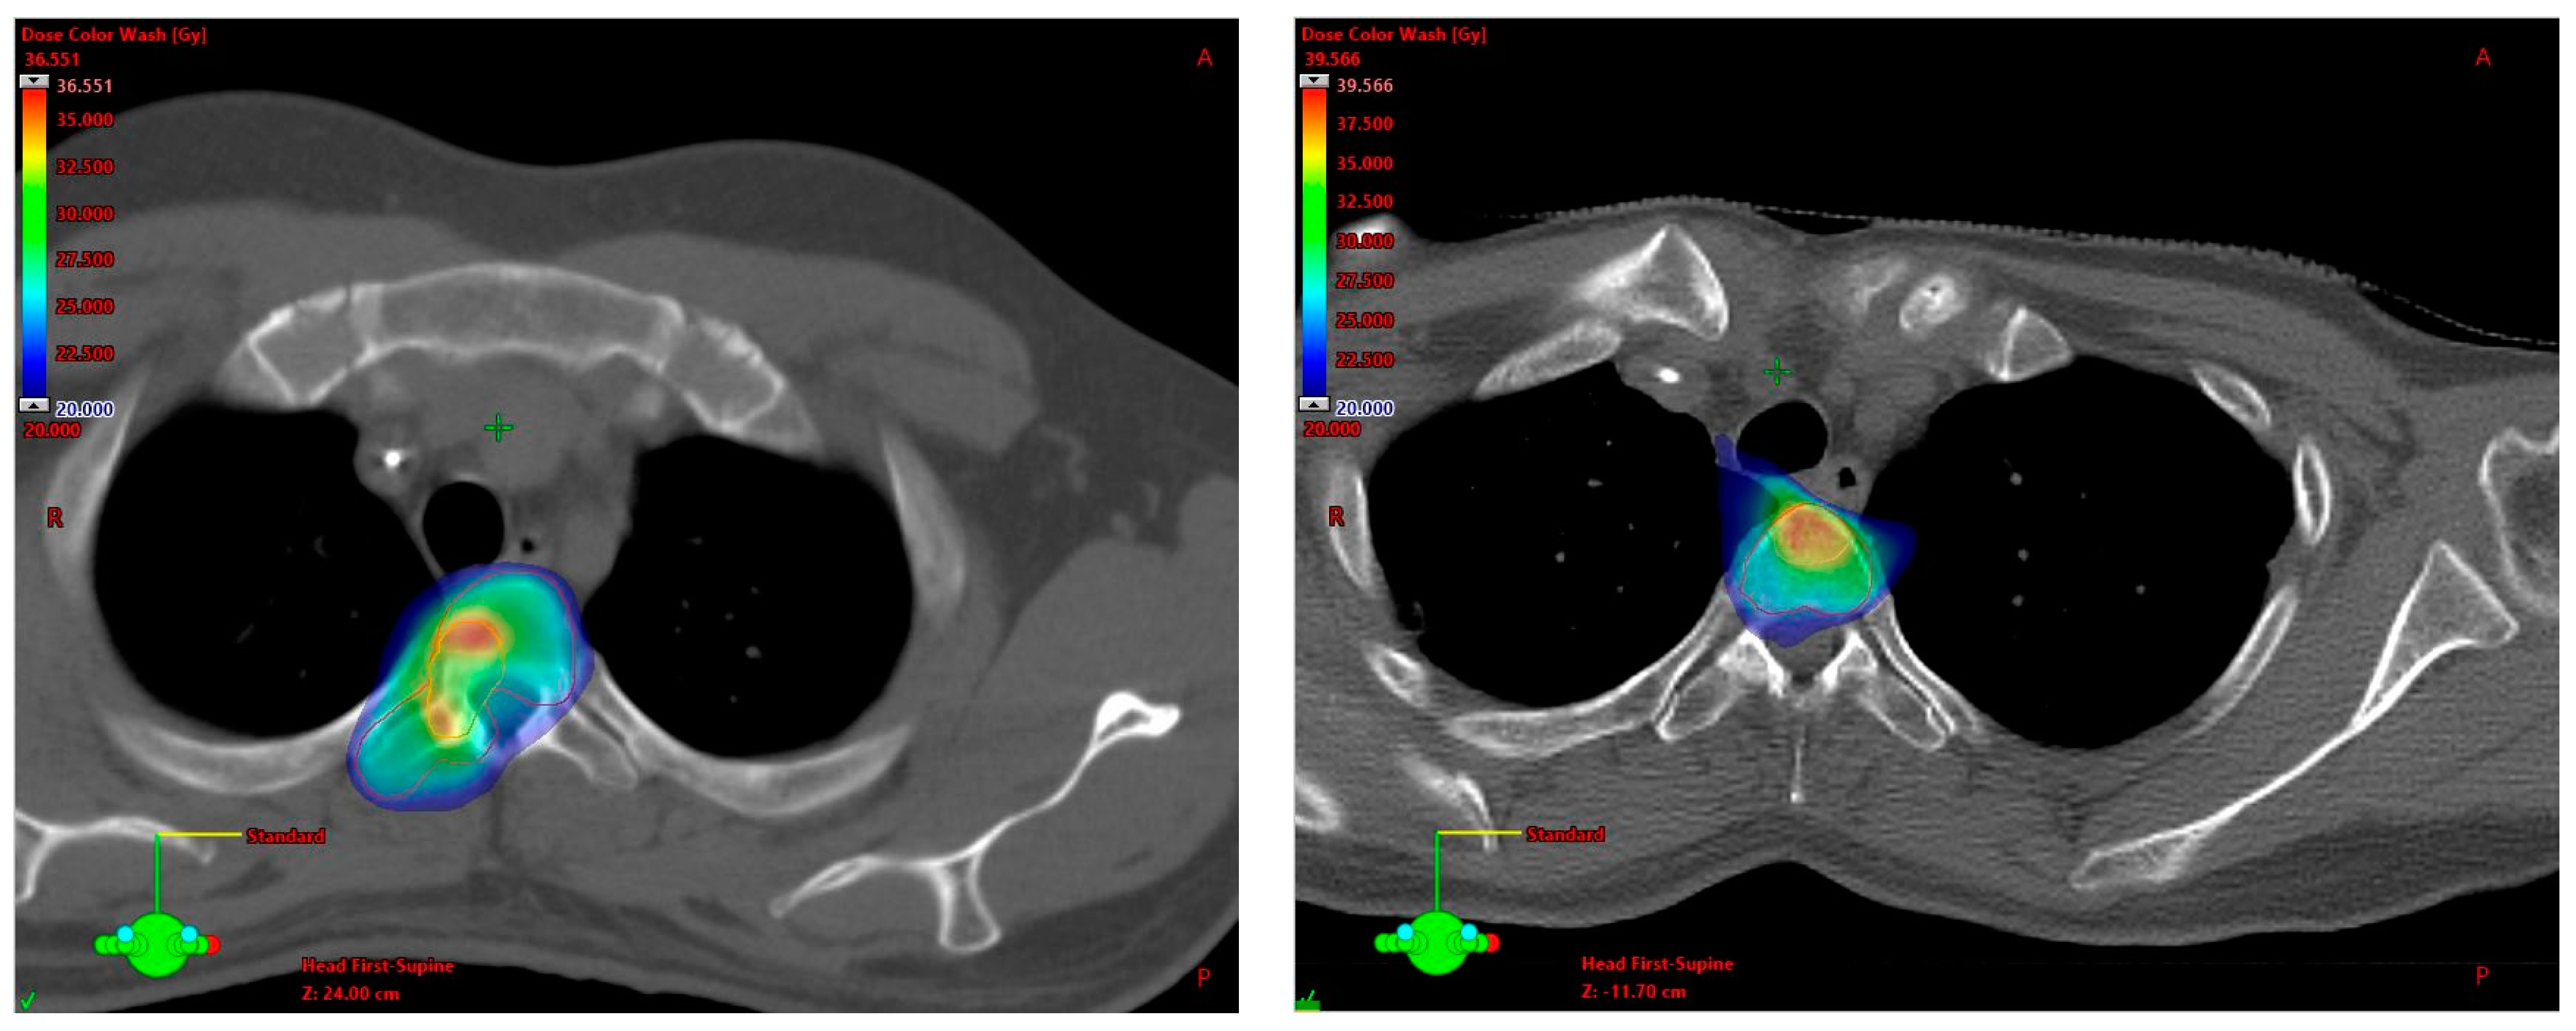

3.2. SBRT Setup, Target Volume Definition and Dose Prescription